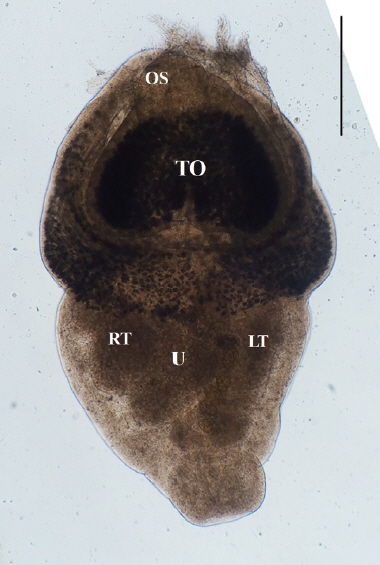

Direct microscopy and PCR were employed to identify the parasitic species. Worms collected from intestines were fixed with 10% neutral buffered formalin under cover glass pressure and identified using microscopy (Fig. 3). Body shape was stout, fleshed, and indistinctly bipartite. Body dimensions were as follows: length 1.77 mm, maximum width at anterior body 1.13 mm, minimum width at hind body 0.38 mm. A small and subterminal oral sucker was located at the end of anterior body. A huge and cordiform tribocytic organ occupied almost the entire anterior body. Two slightly lobulated testes and a coiled uterus were adjacent in the posterior body.